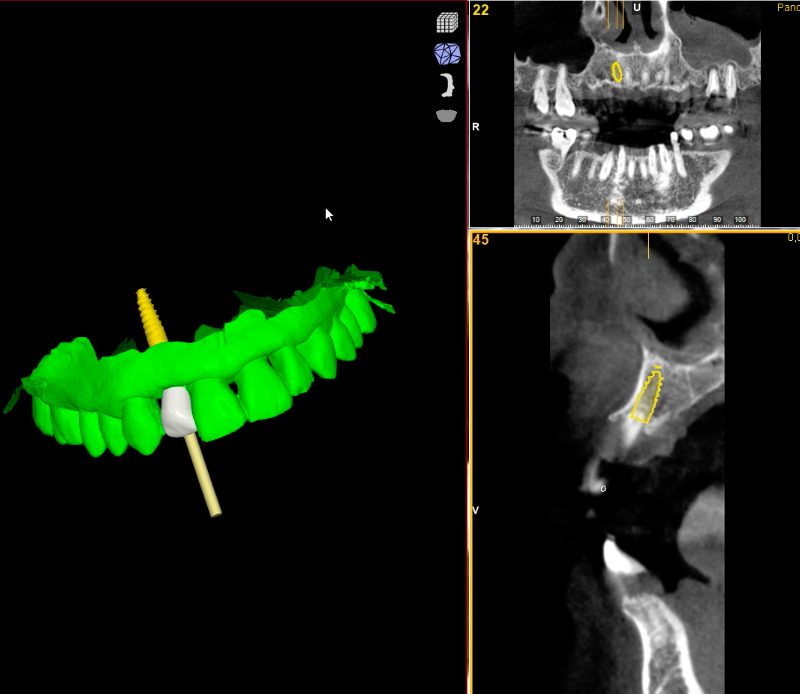

En nuestra clínica de implantes dentales en Las Palmas de Gran Canaria trabajamos con cirugía guiada y planificación digital 3D, lo que nos permite colocar los implantes con máxima exactitud, respetando hueso y tejidos y reduciendo molestias postoperatorias.

Este enfoque avanzado en implantología nos permite prever el resultado antes de la intervención, optimizando estética, funcionalidad y estabilidad a largo plazo. Cada tratamiento es planificado por nuestro equipo especializado en implantología dental en Gran Canaria.

El tratamiento comienza con un estudio clínico completo mediante escaneado digital y diagnóstico radiológico avanzado en 3D. Esto permite valorar hueso y encías y planificar la posición del implante con máxima precisión antes de la intervención.

2. Planificación quirúrgica personalizada

Diseñamos digitalmente la cirugía antes de realizarla, optimizando la trayectoria, el anclaje y el resultado estético final. En implantología avanzada, una buena planificación es la base para lograr previsibilidad y estabilidad a largo plazo.